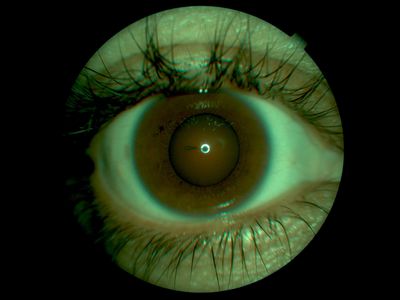

Penetrating corneal stick injury1

Px gardening, bent down and recieved stick injury from Yucca/cactus plant. Endothelium projecting into anterior chamber.